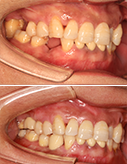

畸形牙阻事业发展,矫正牙重现自信微笑